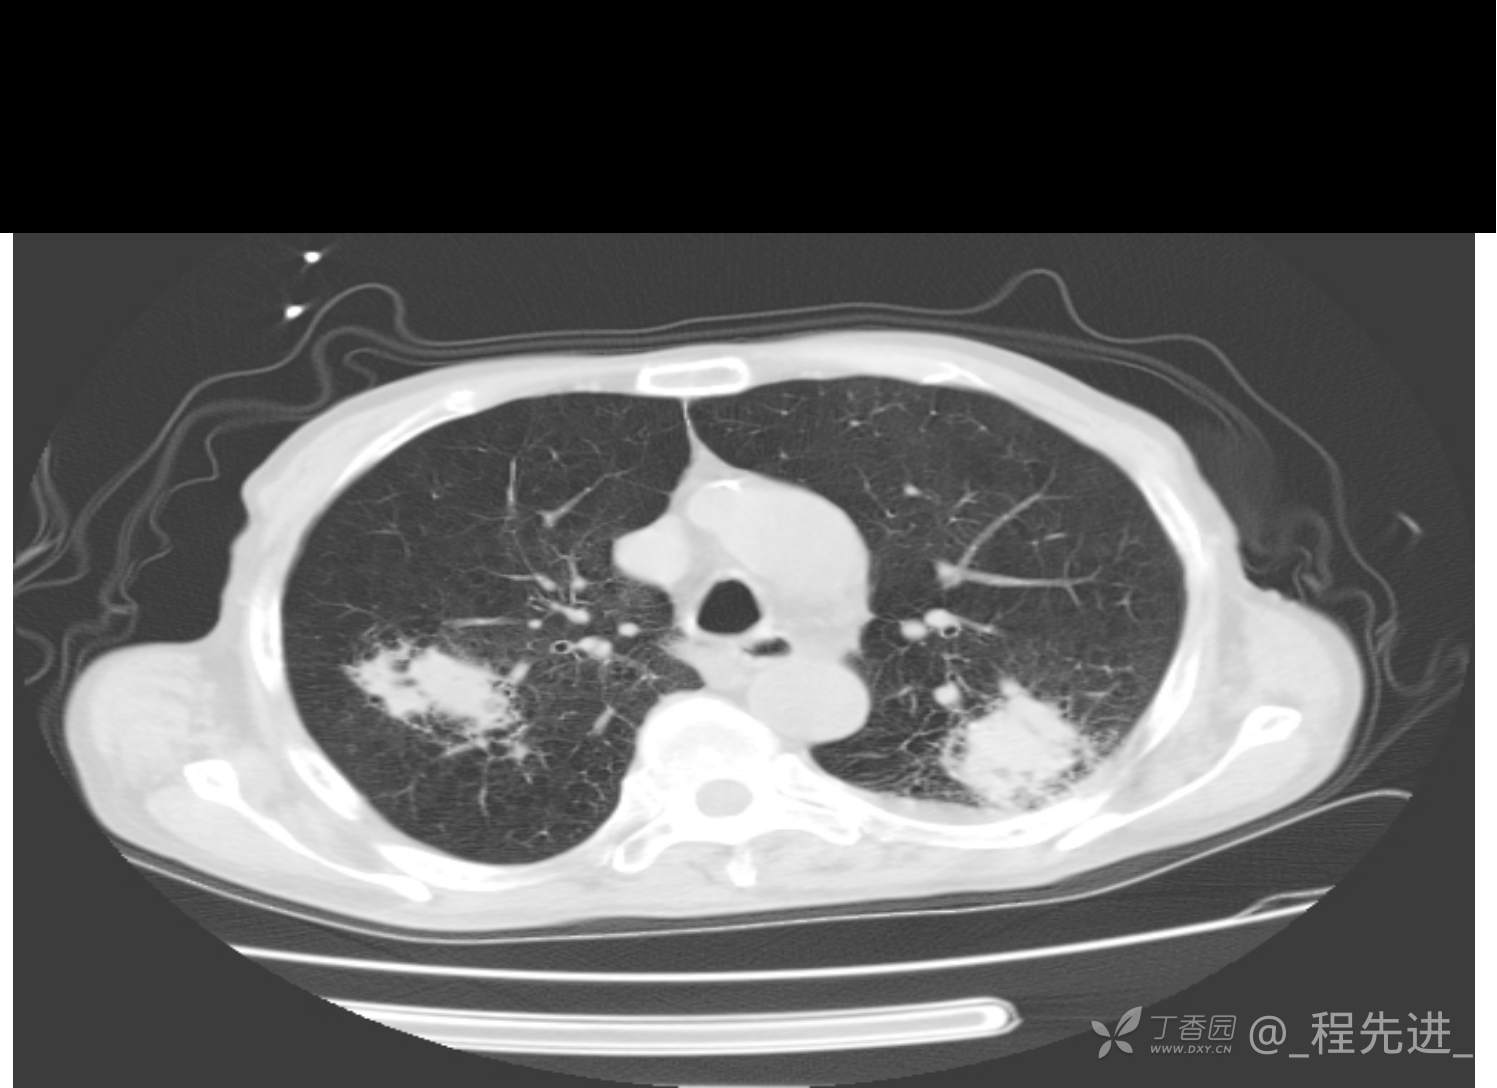

患者性别:男

患者年龄:81岁

简要病史:反复咳嗽、咳痰20余年,加重1周。两肺呼吸音低,可闻及散在干湿啰音。